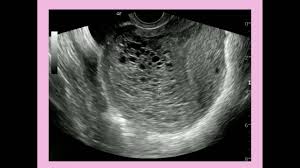

Ultrasound remains the radiological investigation of choice for initial.

The latter four entities are referred to as gestational trophoblastic neoplasia GTN. A common characteristic of all gestational trophoblastic disease is an abnormal proliferation of trophoblast but different components predominate in different tumors. Ultrasound remains the radiological investigation of choice for initial. Gestational trophoblastic neoplasia GTN encompasses a broad spectrum of placental lesions from the pre-malignant hydatidiform mole complete and partial through to the malignant invasive mole choriocarcinoma and rare placental site trophoblastic tumour PSTT. The latter four entities are referred to as gestational trophoblastic neoplasia GTN. There are several histologically distinct types of GTD that range from premalignant complete and partial hydatidiform moles HMs to malignant diseases also known as gestational trophoblastic. Ultrasound in the Diagnosis and Management of GTN Gestational trophoblastic neoplasia GTN includes invasive mole choriocarcinoma PSTT and ETT. Because it is an unusual and serious disease that affects women of reproductive age as well as because its appropriate treatment results in high cure rates it is crucial that radiologists be familiar with gestational trophoblastic disease in order to facilitate its early diagnosis and to ensure appropriate follow-up imaging. Gestational trophoblastic disease GTD is a spectrum of both benign and malignant gestational tumors including hydatidiform mole complete and partial invasive mole Choriocarcinoma placental site trophoblastic tumor and epithelioid trophoblastic tumor.